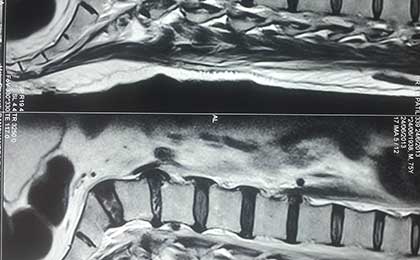

SEQ DISC 3

MYELO OF SEQ DISC 3